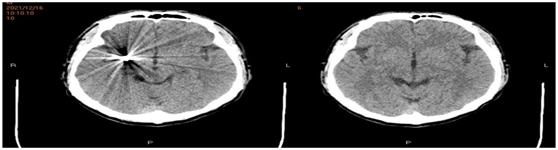

我们正确选择微创介入治疗,不需要开颅,尽可能的减少患者的副损伤,手术顺利,动脉瘤完全填塞,术后复查头颅CT,患者没有再出血。

患者术后病情恢复也一样的顺利,一周后复查头颅CT,颅内出血已经完全吸收(见下图),患者选择出院回家修养。